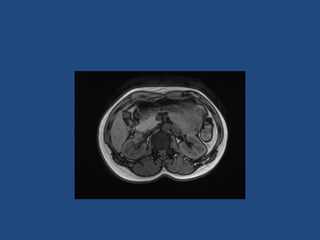

• CT better at eliminating malignancy

(dedicated CT looking at Hounsfield units (HU)

and washout characteristics)

– <10HU = benign (sens 71%, spec 100%)

• MRI may characterise phaeos better

• FDG-PET good for phaeos and cancer

• FNA – consider if cancer history and >10HU on CT

after exclusion of phaeo

Imaging

•

>6cm high suspicion of malignancy

3-6cm repeat imaging in 3-6M

Delayed washout on contrast is suggestive

most are often inhomogeneous, irregular

margins

• Look for invasion of IVC

• Always do CAP and consider bone scan and

pet if in doubt

• Don’t ever biopsy (tumour spill)